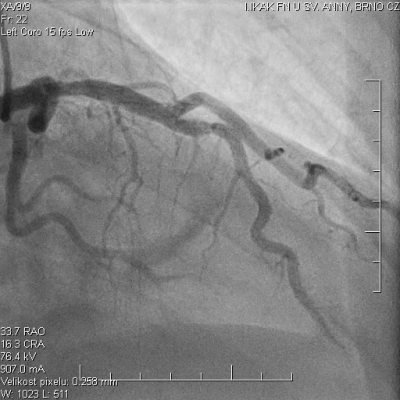

Pacient ve věku 45 let byl referován do našeho kardiocentra po mimonemocniční zástavě oběhu v terénu. Iniciálním nálezem na elektrokardiogramu (EKG)na místě zásahu byla fibrilace komor, byla poskytnuta rozšířená neodkladná resuscitace včetně orotracheální intubace a srdeční defibrilace s obnovením spontánní cirkulace do dvanácti minut. Emergentní selektivní koronarografie neprokázala žádnou významnou stenózu koronárních tepen (video 1, 2, 3), při ventrikulografii byla patrná globální hypokontraktilita levé komory, akcentovaná v oblasti spodní stěny srdeční s celkovou ejekční frakcí levé komory 30 %. V laboratorním nálezu byla s odstupem zjištěna elevace troponinu T stanoveného vysoce senzitivní metodou (hsTnT) – 3 500 ng/l (referenční rozmezí 14 ng/l) a elevovaný C-reaktivní protein (CRP) – 9,3 mg/l (referenční rozmezí 5 mg/l). Anamnéza pacienta zahrnuje bronchiální astma a nosní polypy s medikamentózní terapiísalmeterol/fluticason a omeprazol. Pacient je nekuřák, bez anamnézy abúzu drog.

Na základě těchto výsledků pacient podstoupil opakovanou koronární angiografii, kde byl oproti prvotnímu nálezu pozorován fokální spasmus na ramusinterventricularisanterior (RIA), s jeho úplným odezněním po intrakoronární aplikaci nitrátů (video 4, 5).

V následujících hodinách po výkonu dochází k rozvoji silných bolestí na hrudi jen s částečným odezněním po sublingválním podání nitrátů, na EKG jsou přítomny deprese úseku ST s následnými elevacemi úseku ST ve spodních svodech. Bolesti neustupují ani přes kontinuální intravenózní podávání nitrátů, pacient byl odeslán k provedení emergentní rekoronarografie (celkem třetí v pořadí) s nálezem mnohočetných kritických fokálních spasmů omezujících průtok ve více koronárních povodích (video 6, 7), s jejich postupným úplným odezněním po intrakoronární aplikaci nitrátů a diazepamu (video 8, 9).